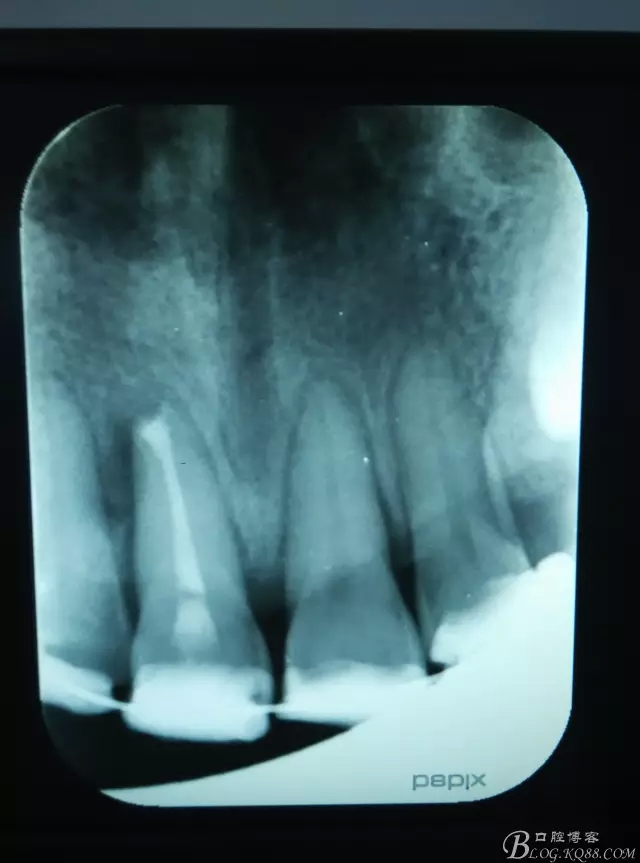

圖1.術(shù)前根尖片顯示11糊劑和牙膠尖均超填,根尖區(qū)及近中有橢圓骨吸收